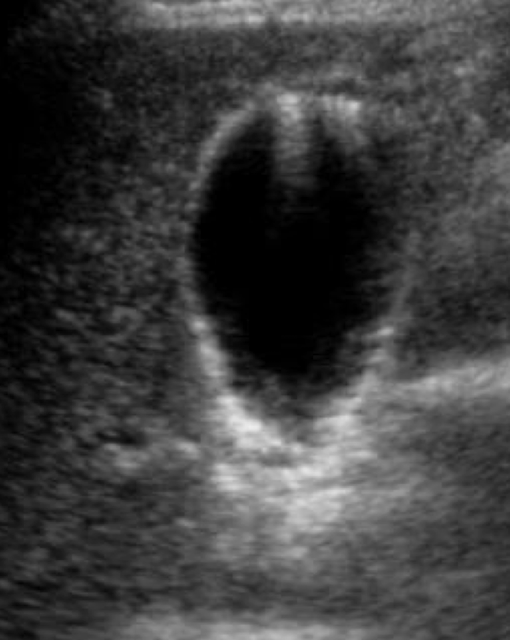

SONO: gallbladder

anechoic, pear-shaped structure

bright echogenic walls

GB wall <3 mm

measured from outer-to-outer